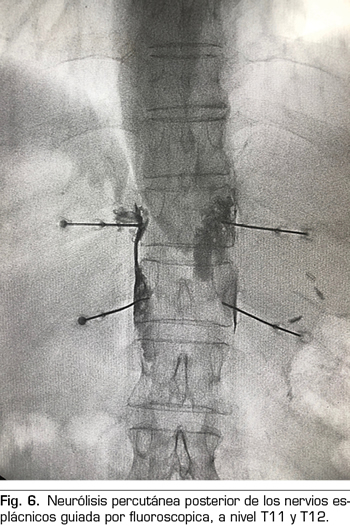

Se realiza mediante un abordaje posterior retrocrural, normalmente guiado por fluoroscopia (Figura 6). Las lesiones pueden llevarse a cabo mediante radiofrecuencia convencional o utilizando agentes neurolíticos como en el plexo celiaco.

– Los nervios esplácnicos son tres nervios que nacen de la cadena simpática torácica y se disponen lateralmente en la columna vertebral: 1) el esplácnico mayor se forma por las fibras preganglionares simpáticas de T5 a T9; 2) el esplácnico menor se forma por las fibras procedentes de T10 y T11; y 3) el esplácnico inferior, por las fibras que vienen de T11 y T12. Todos ellos confluyen en la cara lateral de las vértebras T11 y T12 −lugar idóneo para la realización de una neurólisis− y discurren paralelos hasta atravesar el diafragma y unirse al plexo celiaco.